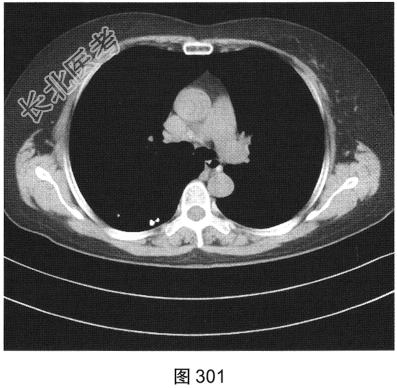

- 多项选择题3.[提示]HRCT图像如图298~图301所示。从患者的HRCT图像中可见哪些阳性征象( )

A、双侧腋窝及纵隔内多发增大淋巴结

B、双肺多发薄壁透亮影

C、小叶间隔增厚

D、右肺多发钙化结节灶

E、双肺多发磨玻璃样密度影

F、支气管扩张